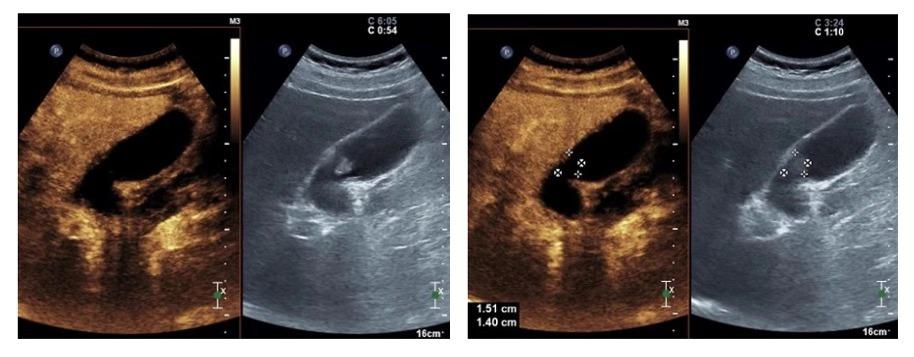

进行胆囊脂餐实验,让患者口服油腻食物,半个小时后再行超声检查,通过前后胆囊的大小变化来判断胆囊的收缩功能。

由此可得,该患者胆囊收缩率约为80%,胆囊收缩功能正常,具有保留胆囊的意义。(一般情况下缩小50%以上,可视为胆囊收缩功能正常)

术后患者未出现胆囊穿孔、出血等明显并发症,精神状态良好。观察一天后给予超声造影检查:

可见占位未见强化,已完全“灭活”,胆囊壁水肿消失,恢复了正常厚度,胆囊壁未受明显损伤。次日活检病理提示:胆囊幽门腺腺瘤。